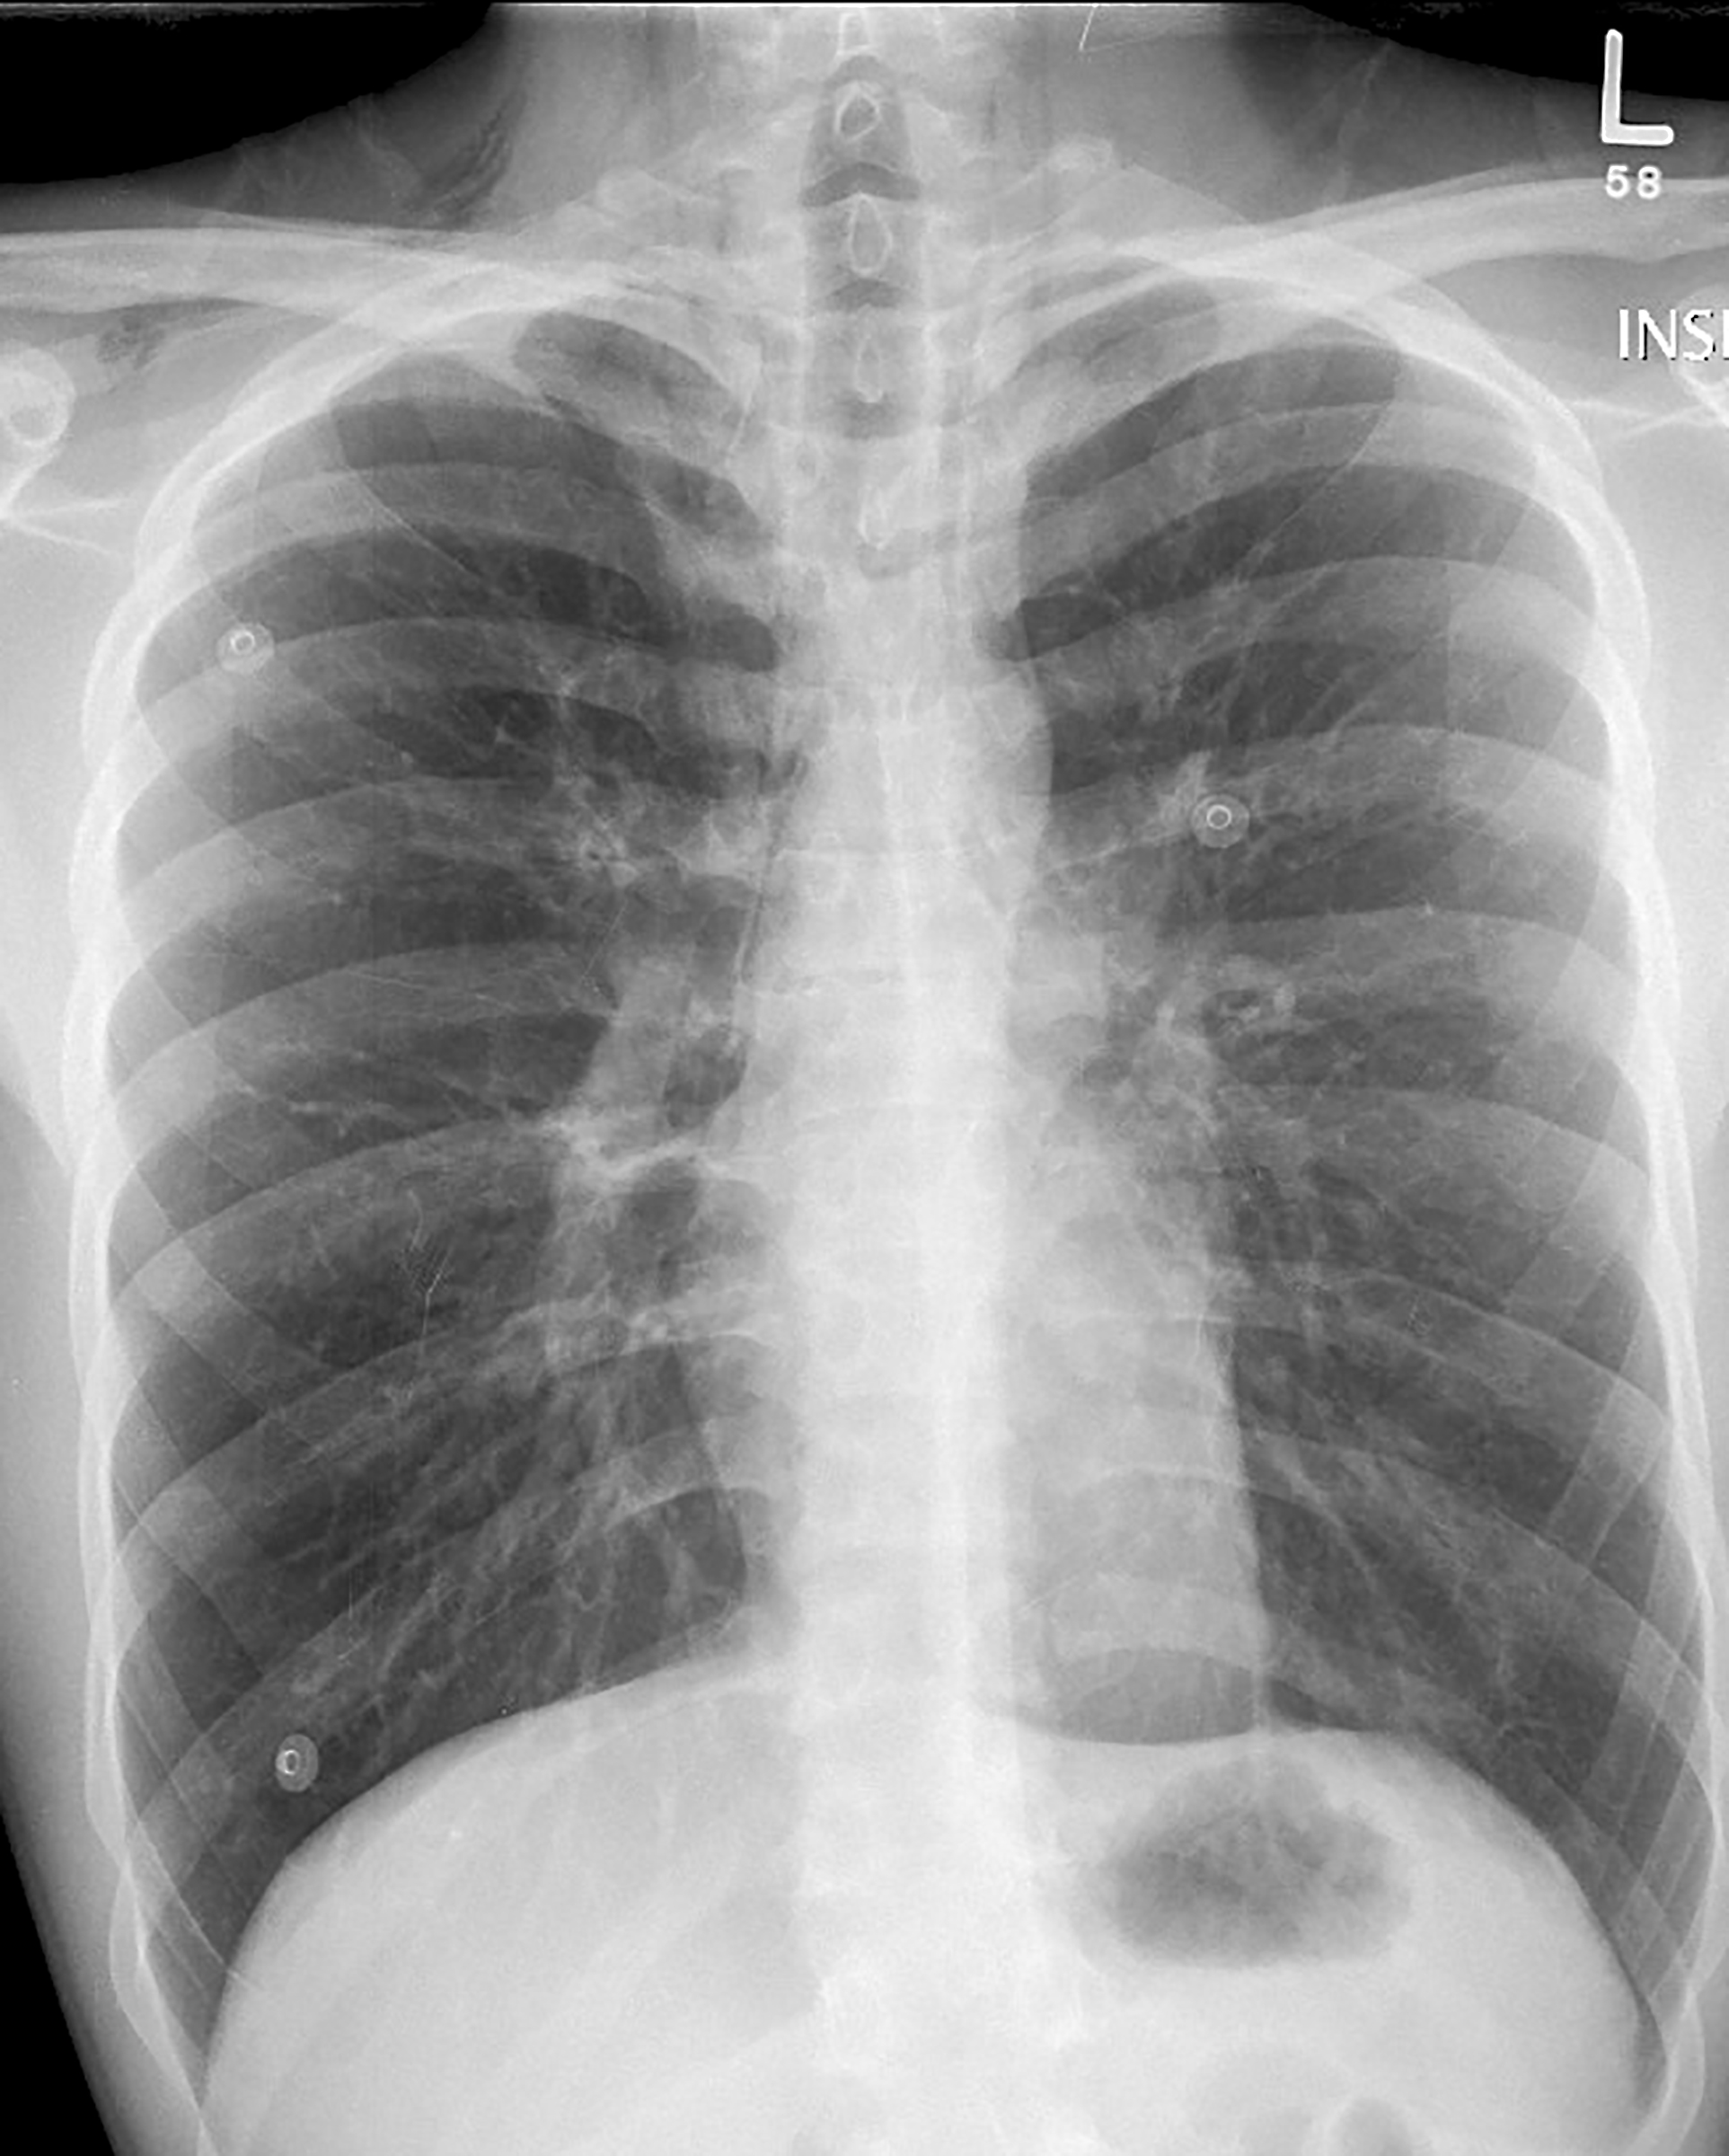

Asthmatic pneumomedistinum PA

Asthma PnMed PA